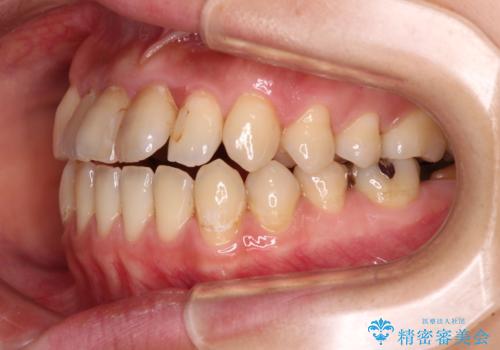

- 上下前歯の開咬とデコボコを気にして来院された患者様です。

開咬(オープンバイト)はインビザラインによる矯正治療がワイヤー装置と比べて圧倒的に有利であるため、インビザラインによる矯正治療を行うこととしました。

通院されなかった時期があって治療期間が長くなったり、奥歯に抜歯が必要な歯があったりと、治療は一筋縄にはいきませんでしたが、何とか治療を終えることができました。

今後はインプラント治療やむし歯治療を進めて行く予定です。